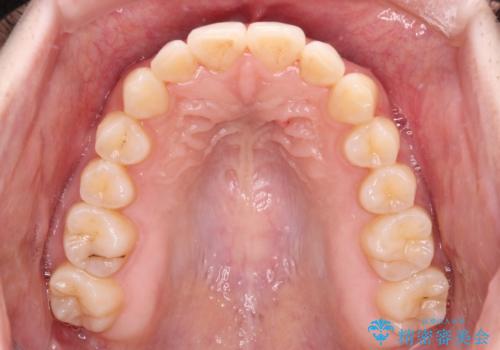

ワイヤー矯正へ変更してからはあっという間に治療が進み、1年弱で終えることができました。

- 治療期間

- 2年2ヶ月